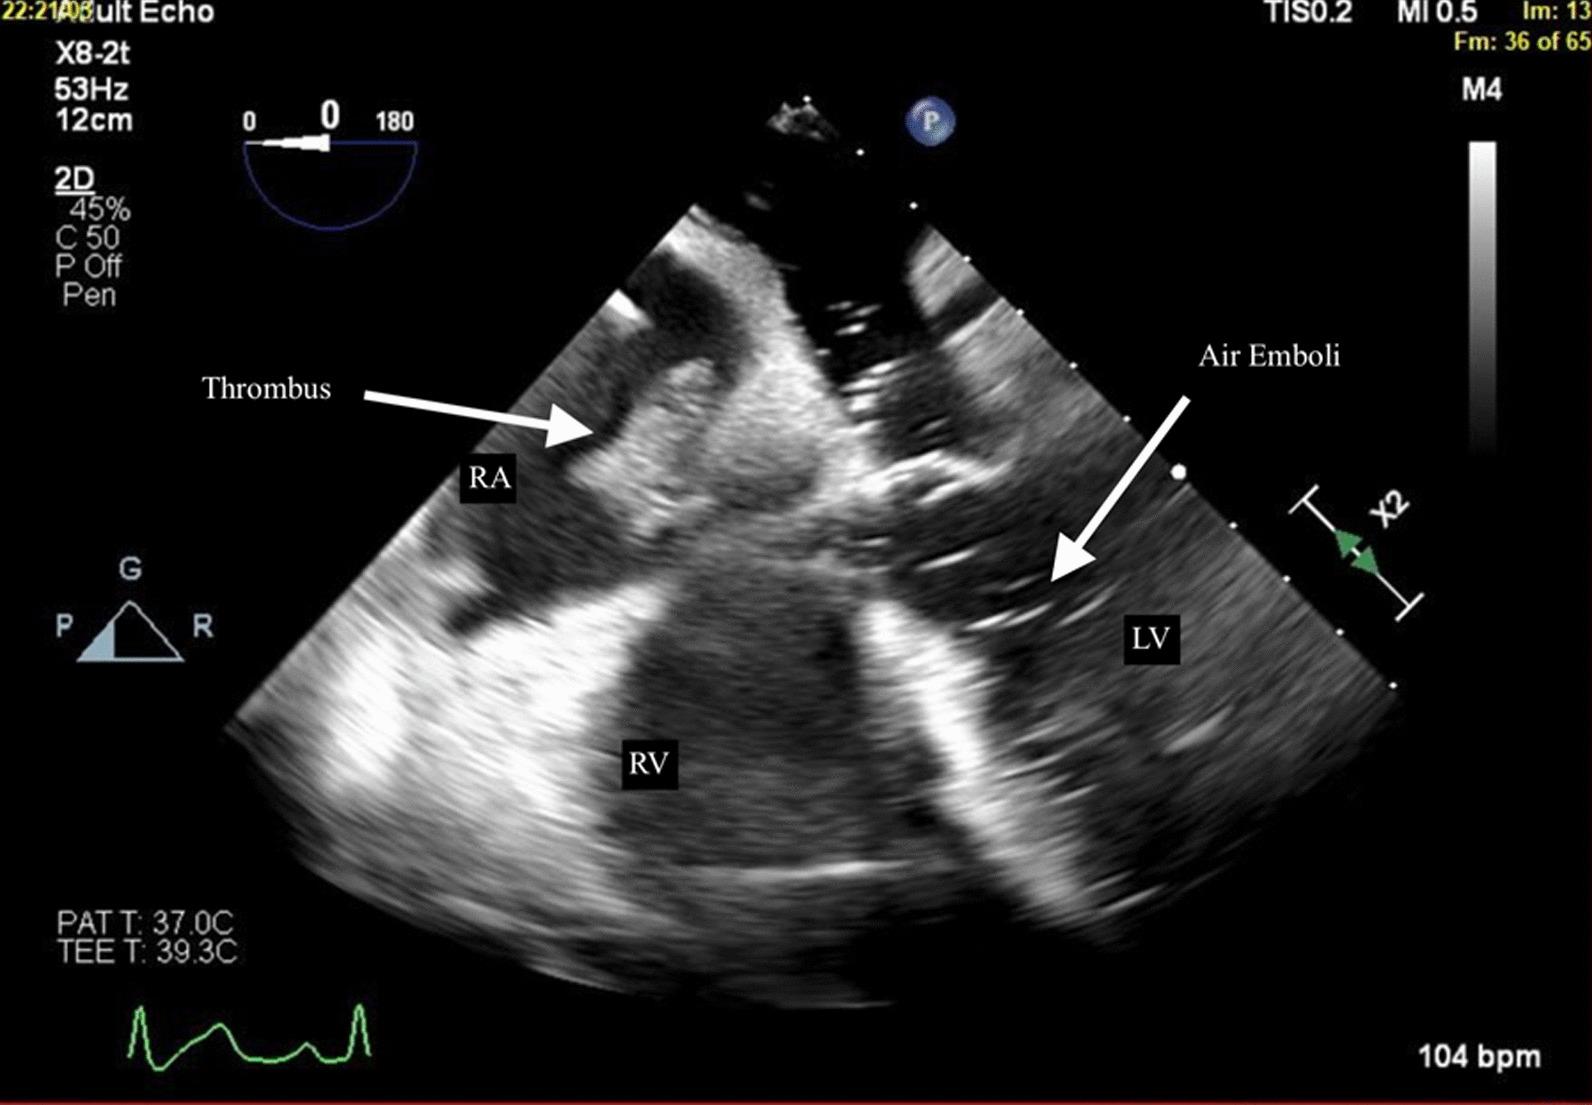

This case report outlines the clinical course of a 60-year-old white female patient with end-stage liver disease complicated by portal hypertension, ascites, and hepatocellular carcinoma. The patient underwent orthotopic liver transplantation and encountered concurrent intraoperative complications involving intracardiac thrombus and vascular air embolism. Transesophageal echocardiography revealed the presence of air in the left ventricle and a thrombus in the right atrium and ventricle. Successful management ensued, incorporating hemodynamic support, anticoagulation, and thrombolytic therapy, culminating in the patient's discharge after a week.

本病例报告概述了一位 60 岁白人女性患者的临床病程,该患者患有终末期肝病,伴有门静脉高压、腹水和肝细胞癌。该患者接受了原位肝移植,并在术中遇到了涉及心内血栓和血管空气栓塞的同时性并发症。经食管超声心动图显示左心室存在空气,右心房和心室存在血栓。通过血流动力学支持、抗凝和溶栓治疗成功进行了管理,患者在一周后出院。